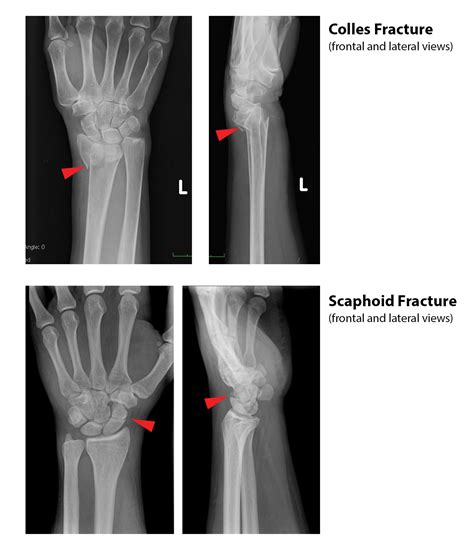

Human Upper Limb Bones Anatomy Medical Stock Illustration 2509536475 ...